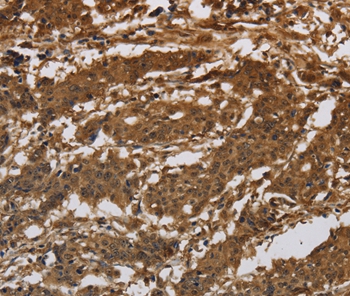

Immunohistochemical analysis of paraffin-embedded Human gastric cancer tissue using #37662 at dilution 1/30.

Immunohistochemistry: 1:50-1:200